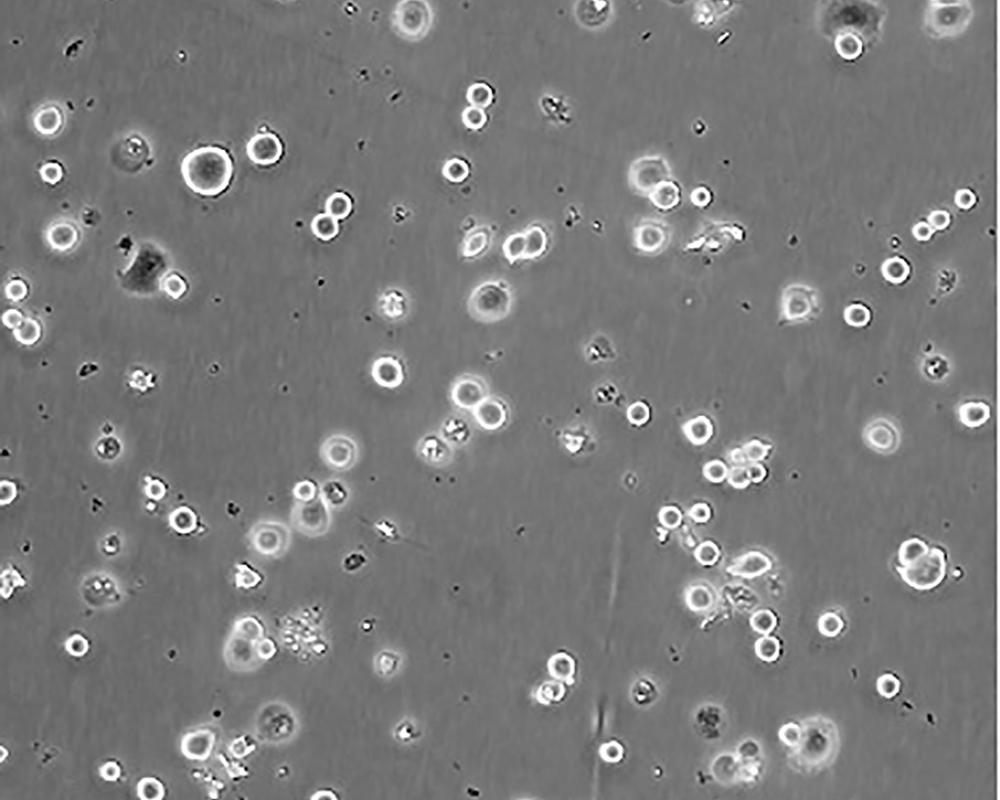

SK-BR-3 [SKBR-3;SKBR3]

產品名稱 SK-BR-3 [SKBR-3;SKBR3]

中文名稱 人乳腺腺癌細胞

組織來源 mammary gland/breast; derived from metastatic site: pleural effusion

細胞種屬 Homo sapiens, human

生長特性 adherent

形態特征 epithelial

細胞描述 he patient, a White, Caucasian female, age 43, blood type A+, had been treated with radiation, steroids, cytoxan and 5-fluorouracil.No virus particles.Ultrastructural features include microvilli and desmosomes, glycogen granules, large lysosomes, bundles of cytoplasmic fibrils.The SKBR- 3 cell line overexpresses the HER2/c-erb-2 gene product.